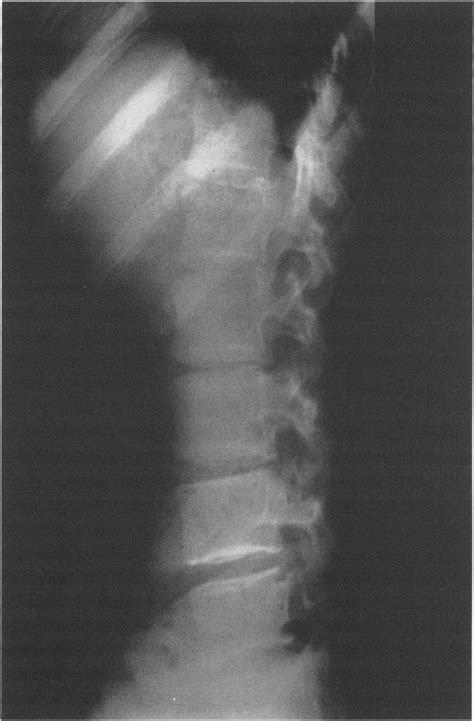

Que es discartrosis lumbar. Síntomas y tratamientos - Columna Vertebral

WebLa discartrosis hace referencia a la degeneración de los discos intervebrales, que puede deberse a: actividades que favorecen su desgaste, lesiones, desecación del. WebContribuye a la mejora de la postura, ya que caminando se trabaja la lordosis lumbar y cervical, así como la cifosis dorsal. Fortalece la musculatura de los. WebEsto se debe a que la región lumbar es la que más carga lleva. Un estilo de vida sedentario o una mala postura pueden influir en el desarrollo de esta patología. La. WebEn resumen, andar no es malo para el lumbago si se hace de forma moderada y cuando no cause dolor. Pero no es el ejercicio más eficaz para tratar el. WebLa estenosis espinal lumbar es el estrechamiento del área del canal espinal en la parte baja de la espalda. Tal estrechamiento se debe a problemas como la enfermedad. WebLa discartrosis lumbar es una patología que suele ir acompañada de otras patologías de la columna: Degeneración de disco. Estenosis espinal. Los síntomas de la. WebLas distensiones de la espalda con frecuencia se curan por sí solos, con la ayuda de alguna combinación de descanso, aplicación de hielo o de calor, antinflamatorios, estiramientos. WebCaminar es bueno porque has de moverte para fortalecer los músculos y oxigenarlos. Es muy importante que evites el sedentarismo, y verás como pronto.

WebLa discartrosis de la columna lumbar se observa con mayor frecuencia en pacientes de edad avanzada, pero tambi é n se puede ver en todos los grupos de edad. Los. WebLos síntomas de la artrosis lumbar son el dolor, la rigidez y la limitación de la movilidad. El síntoma más frecuente de la artrosis lumbar es el dolor de características mecánicas,. WebEl motivo es que reforzar los músculos del abdomen será positivo para que la zona lumbar esté más protegida cuando realices esfuerzos que impliquen el.